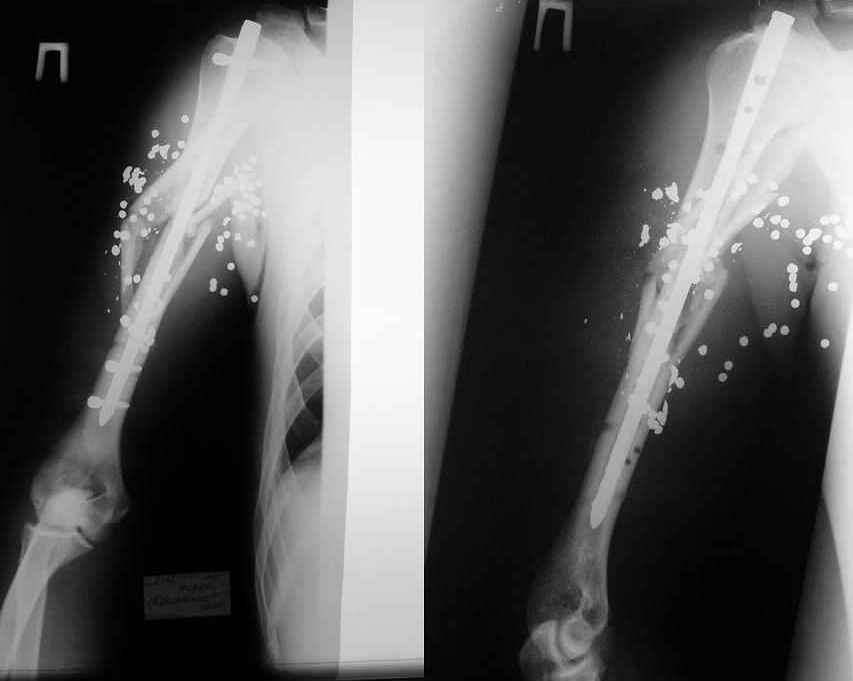

Ув. Михаил Викторович. Вы писали, что около 10 лет применяете стержневые аппараты, но они не обладают репозиционными возможностями. У нас был

разработан такой аппарат (авторы: Тауфик Амро, Сушко Геннадий Александрович (ученик Илизарова)). Манипулируя узлами данного аппарата возможно закрыто устранить любые смещения, за исключением ротационных.

Высылаю

видеофайл (несколько неудачный, но смысл понятный) - Аппата Амро широко применяется в Запорожье, Мелитополе, Приморске.

Изготовить его особого труда не составляет. У нас в Приморске своими силами мы изготовили 10 таких. Если Вас это заинтересует - вышлю чертежи, и др. информацию.